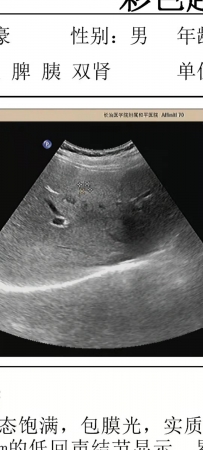

右肝低回声结节,发现后五个月彩超复查无变化,考虑什么?

肝脏低回声结节,界清,无血流信号显示,无肝病史,乙肝有抗体,甲胎蛋白正常,发现时1.0*0.7cm,两月后复查彩超0.9*0.6cm,又过了三个月复查彩超1.0*0.8cm,前后五个月无变化,有不均质脂肪肝背景,五个月减肥后脂肪肝很轻了基本没有,这低回声区像什么?可以排除肝CA吗?

四月份做了5mm增强CT,什么东西也有发现,重新让医生看了彩超,低回声很轻了找了半天才找见,而且这低回声并是不在肝右叶,而是在肝左内叶S4段,医生说可能是肝岛

三个月每天快走半个小时,复查彩超脂肪肝没了低回声区也消失了,证实是肝岛